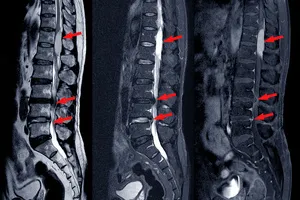

신경외과는 뇌, 척수, 말초신경 등 우리 몸의 신경계 전체를 다룹니다. 허리디스크의 경우 디스크가 신경을 눌러서 생기는 통증, 저림, 마비 등 신경학적 증상에 대한 전문적인 지식과 치료 경험이 풍부합니다. 특히 미세현미경이나 내시경을 이용한 디스크 제거술처럼 신경을 보존하면서 디스크를 제거하는 수술에 능숙하죠. 신경학적 이상 증상이 두드러지거나 MRI 검사에서 신경 압박이 심하게 확인될 때 신경외과 진료가 더 효과적일 수 있습니다.

- 주요 치료: MRI 검사, 신경차단술, 신경성형술, 고주파 수핵 성형술, 적극적인 운동 치료 및 재활